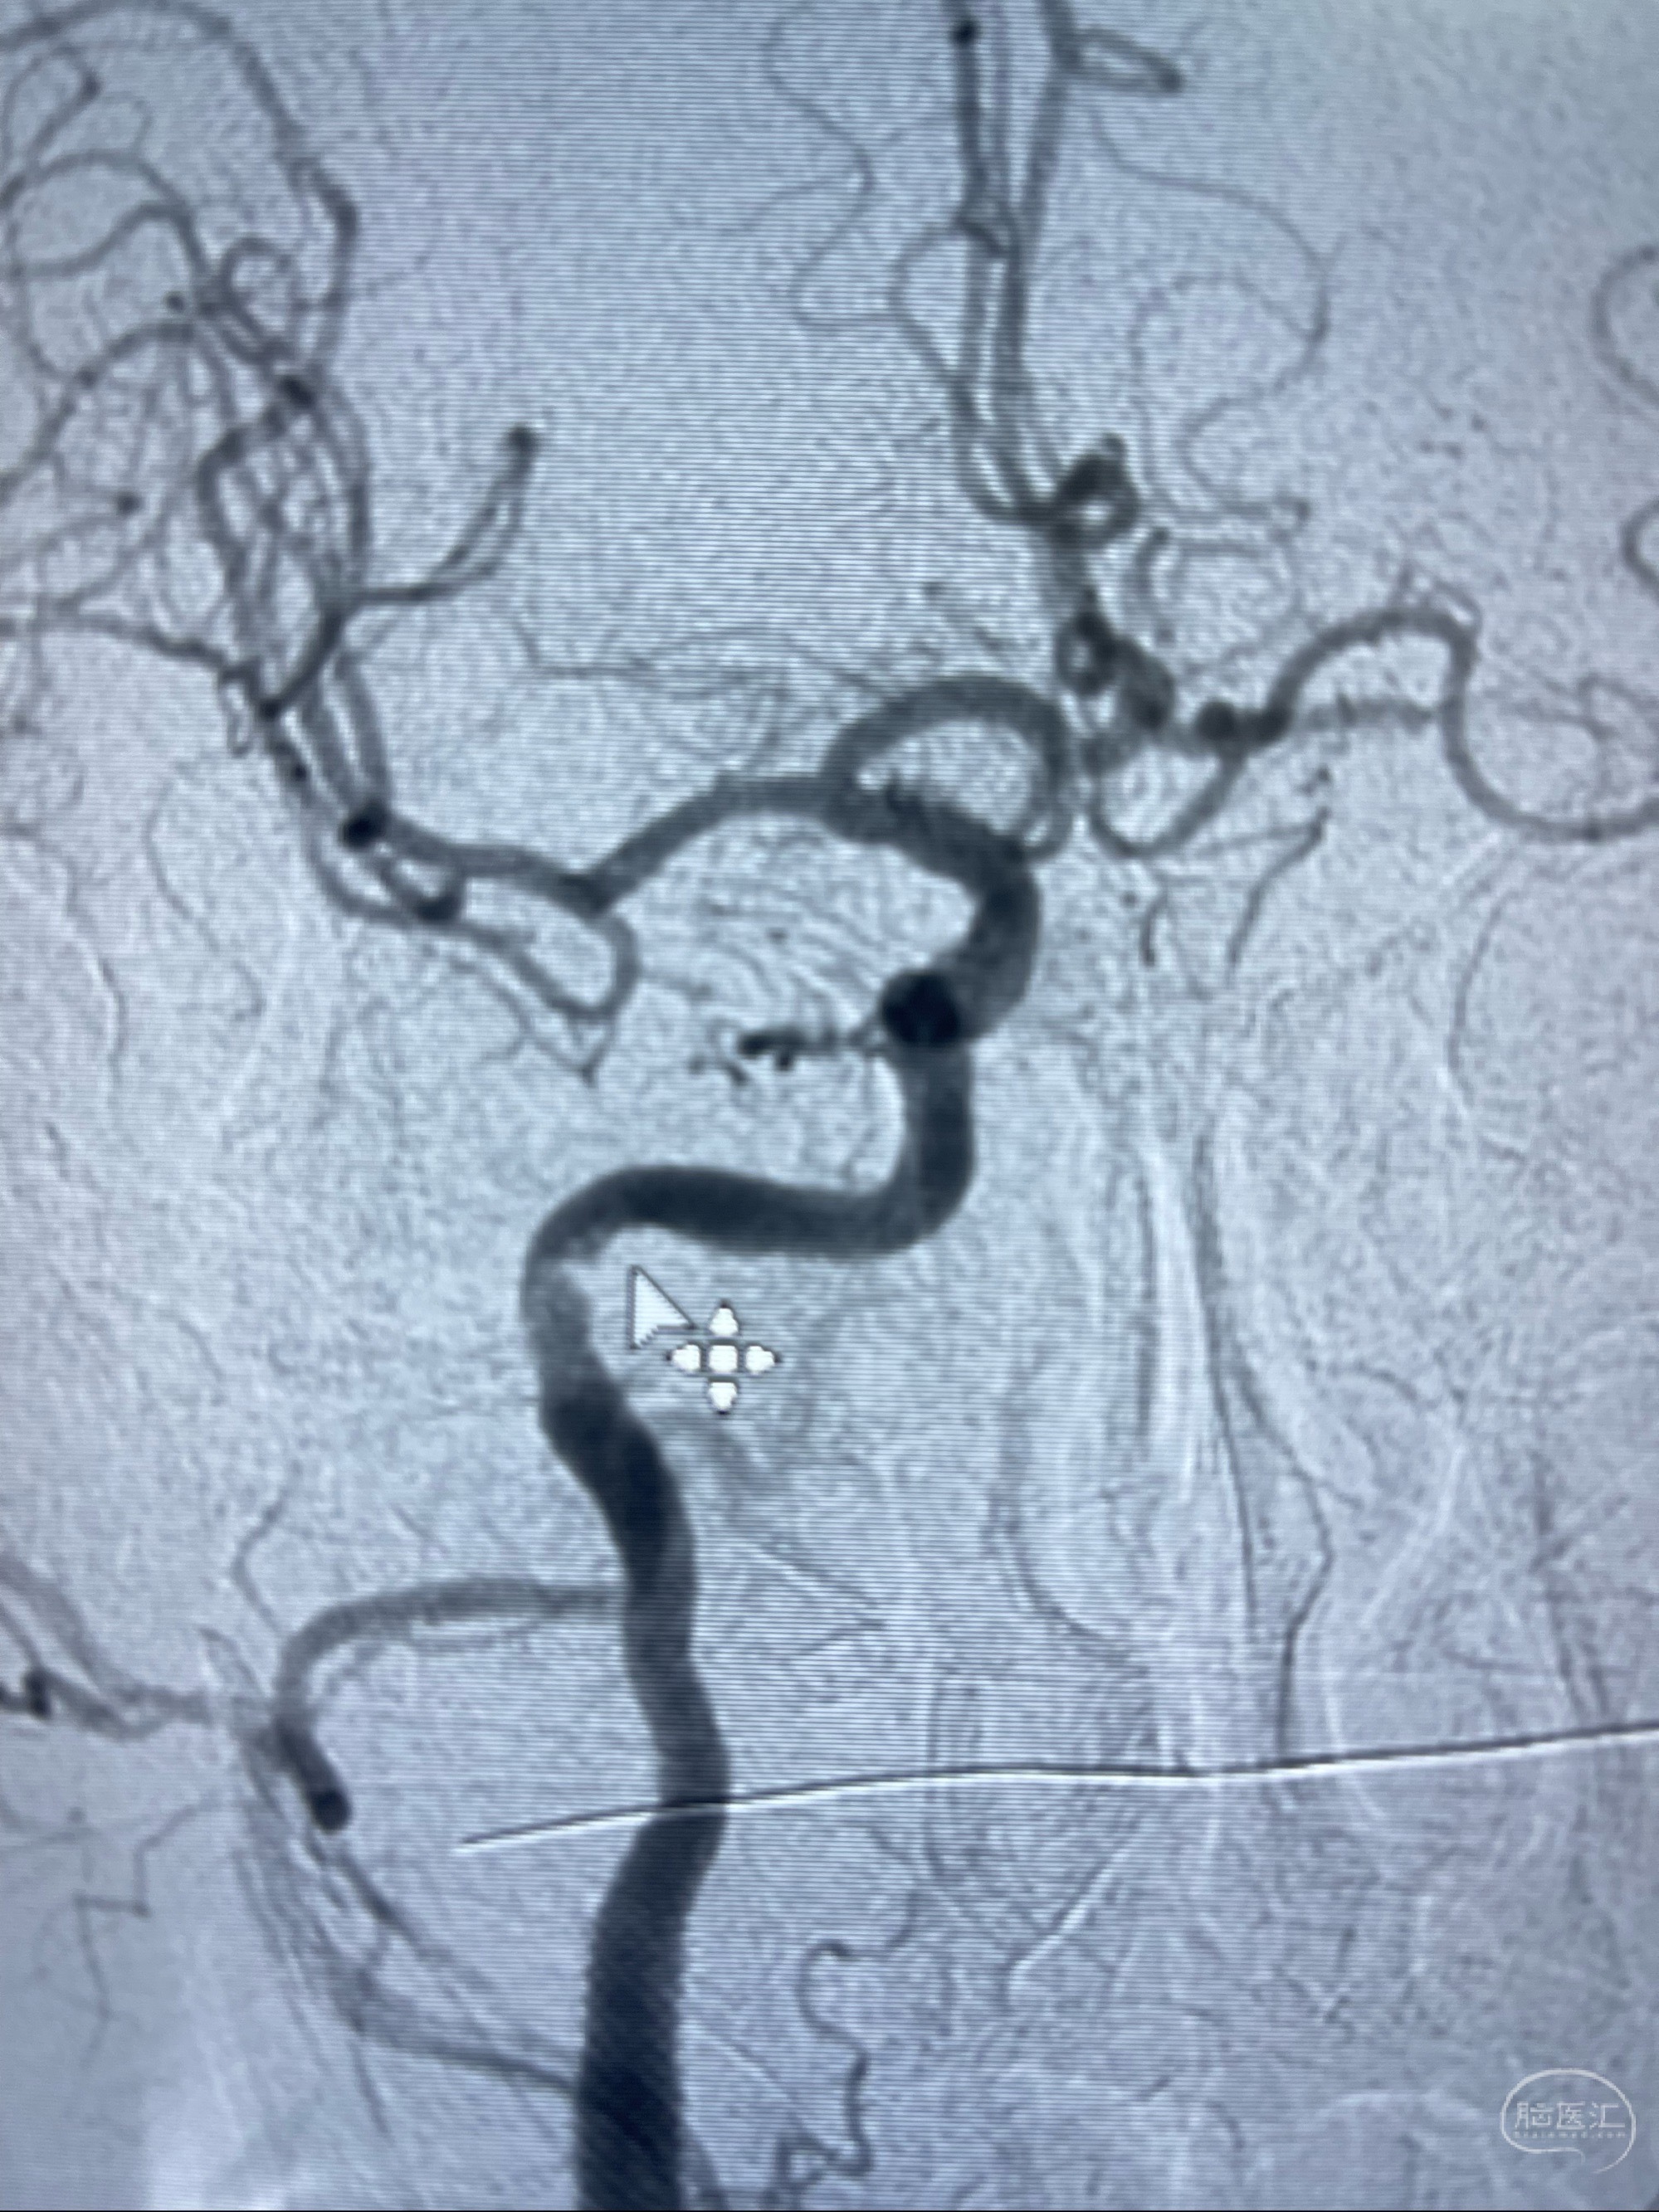

2023-07-10DSA:右侧颈内动脉岩骨段夹层伴中偏重度狭窄改变,左侧颈总动脉闭塞、右侧颈外动脉由右侧肋颈干甲颈干吻合代偿

箭头所示为颈内动脉岩骨段重度狭窄,结合MRI,考虑为肿瘤侵犯右侧颈内动脉

箭头以近至支架段管腔不规则狭窄